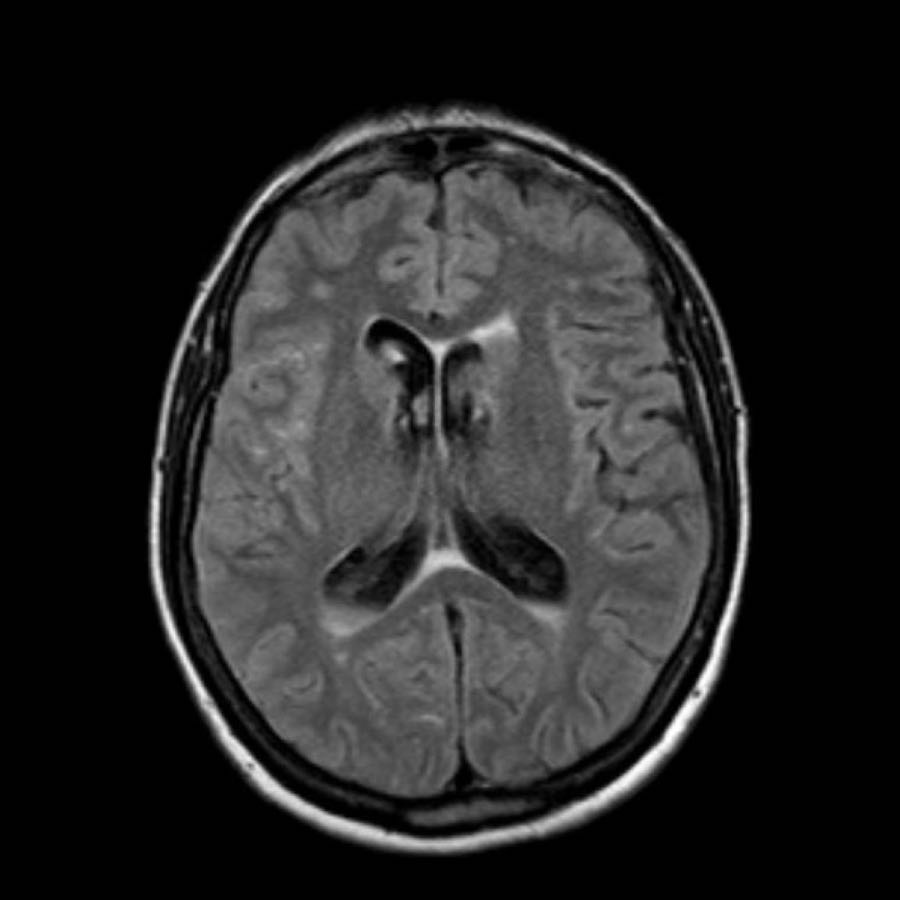

Các hình ảnh cho thấy xuất huyết tại hạch nền ở bệnh nhân tăng huyết áp lâu năm.

Tổn thương nằm tại đầu nhân đuôi.

Đầu nhân đuôi nhận máu từ động mạch Heubner và các động mạch thấu kính-vân.

Vỡ các động mạch này gây xuất huyết nhu mô não.

Sự hiện diện của tụ máu trong não thất được coi là yếu tố tiên lượng xấu do tắc nghẽn lưu thông dịch não tủy gây não úng thủy và tăng áp lực nội sọ.